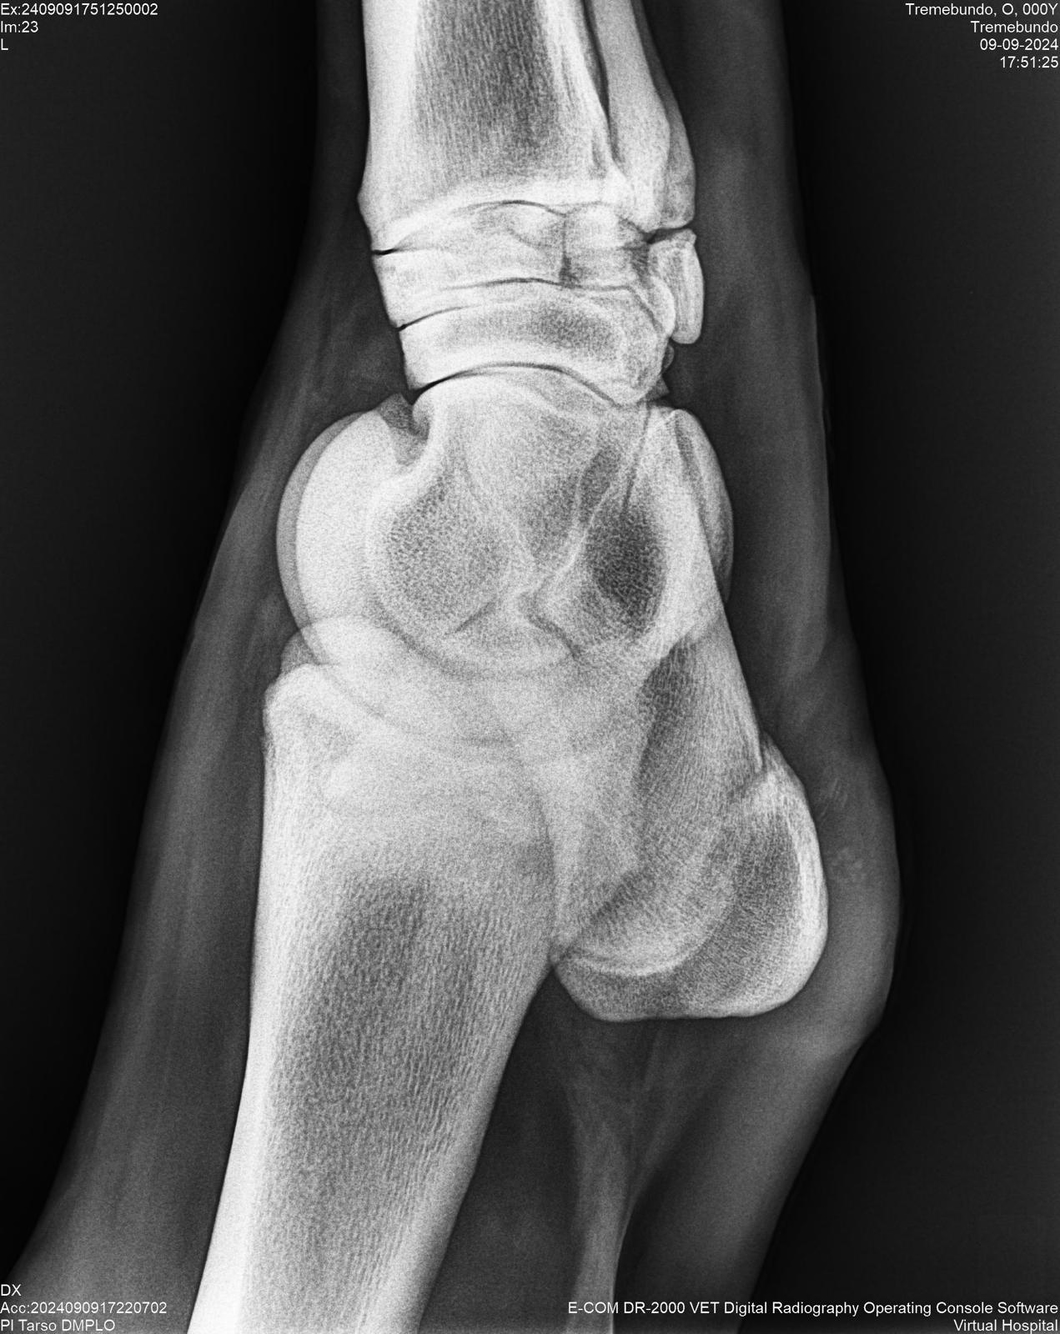

LOTE 37, TREMEBUNDO

Ficha del Lote

Identificador: #291140-

Generacion 2022